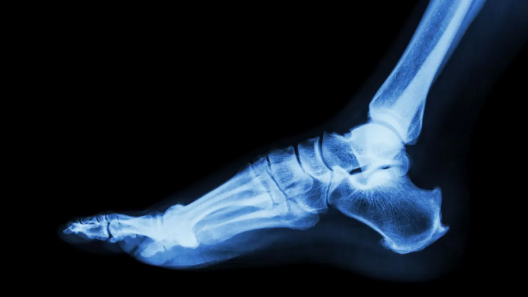

捷迈邦美(Zimmer)目前推出了两款矫形器械,其中包含今年年初以 11 亿美元(约合78亿元人民币)收购的足踝专用器械 Paragon 28。

该公司于周三公布,这些新产品为其产品组合增添了针对胫骨骨折和后足损伤的治疗设备,而推出这些设备也继续彰显了捷迈邦美(Zimmer)保持 Paragon 业务两位数增长,并扩大其运动医学、四肢和创伤(SET)业务的努力。

这些设备可以治疗胫骨骨折和后足损伤

新推出的器械包括Gorilla Pilon融合钢板系统Phantom TTC创伤钉ParagonGorilla系统用于稳定和固定多种骨折。该公司最新版本的器械已于7获得510(k)许可。

捷迈公司在产品发布公告中提到了该装置在胫骨远端骨折(pilon骨折)中的应用。该公司表示,胫骨远端骨折占胫骨骨折的7%10%。部分此类骨折患者需要进行踝关节融合术。

坎贝尔诊所医院骨科部门主任克莱顿·贝廷 (Clayton Bettin) 在一份声明中表示,Gorilla 是市场上第二款专为粉碎性 pilon 骨折的踝关节原发性融合而设计的钢板。

Arthrex 2021 年获得了 510(k)许可Bettin 表示,Gorilla 系统提供了一种低调的选择,它符合解剖学轮廓,能够在两列之间实现稳定固定。

捷迈公司在推出Gorilla的同时,还推出了Phantom TTC创伤钉,后者是一款用于治疗复杂pilon骨折等高难度创伤病例的固定装置。Paragon公司最新款Phantom型号已于今年7月获得美国食品药品监督管理局(FDA)的批准。